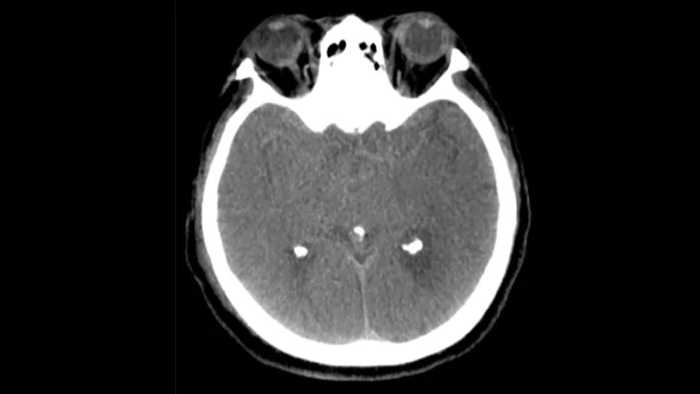

CT-artige Darstellung

SmartCT Soft Tissue generiert eine CT-artige Darstellung des Weichgewebes und erleichtert die Schlaganfalldiagnose auf drei Arten: Ein kontrastmittelfreier Scan hilft bei der Erkennung früher ischämischer Veränderungen. Ein Scan der frühen Phase hilft bei der Identifizierung des proximalen Verschlusses. Ein kontrastmittelverstärkter Scan der Spätphase unterstützt die Erkennung von Kollateralen.

SmartCT Soft Tissue

Verwenden Sie die SmartCT Soft Tissue (CT-artigen) Bilder der Neurovascular Suite zur Beurteilung des Behandlungserfolgs und Überprüfung auf Blutungen.